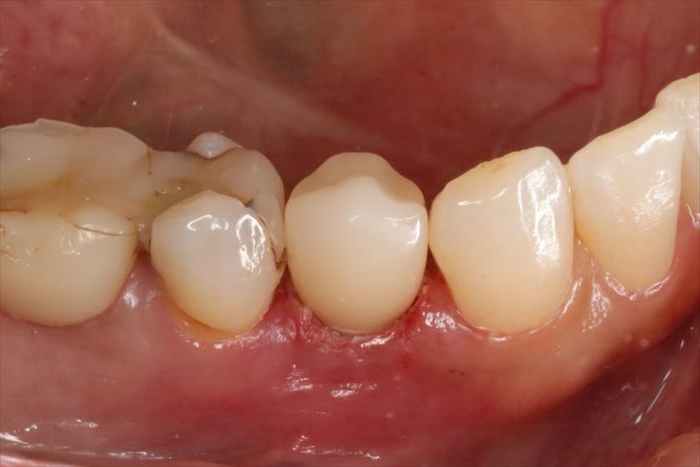

接着直後の状態です。(2025.10.24)

_

接着から4か月経過した状態です。(2026.02.28)

今年は画像左側:右下小臼歯・大臼歯の治療を進めます。